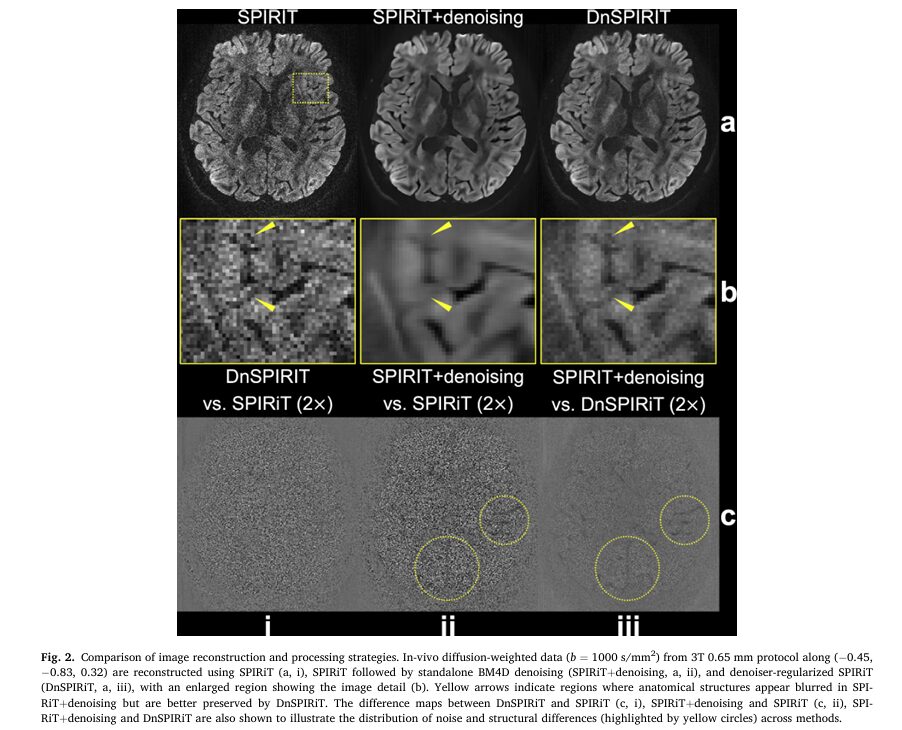

The Post-Processing Blurring Problem

Traditional denoising approaches apply noise suppression as a final post-processing step after image reconstruction. While this improves SNR, it introduces two problems:

- Structural blurring that obscures fine anatomical details

- Quantitative bias that compromises diffusion measurements (fractional anisotropy, mean diffusivity)

The new DnSPIRiT (Denoiser-regularized SPIRiT) framework integrates denoising directly into the k-space reconstruction process, enforcing consistency with acquired data throughout the iteration process.

Performance Advantages

Quantitative comparisons demonstrated DnSPIRiT’s superiority:

- SNR improvement: 66% higher than standard SPIRiT reconstruction

- Angular CNR improvement: 20% higher than standard SPIRiT

- Image sharpness retention: Only 22% blurring loss versus 44% for post-hoc denoising

- Quantitative accuracy: Lowest bias in fractional anisotropy (FA: 0.002 vs. 0.019 for post-hoc denoising)

- Mean diffusivity (MD) fidelity: Best agreement with reference 1.22 mm data

This balanced approach delivers SNR benefits while minimizing the structural alterations that compromise anatomical and quantitative accuracy.